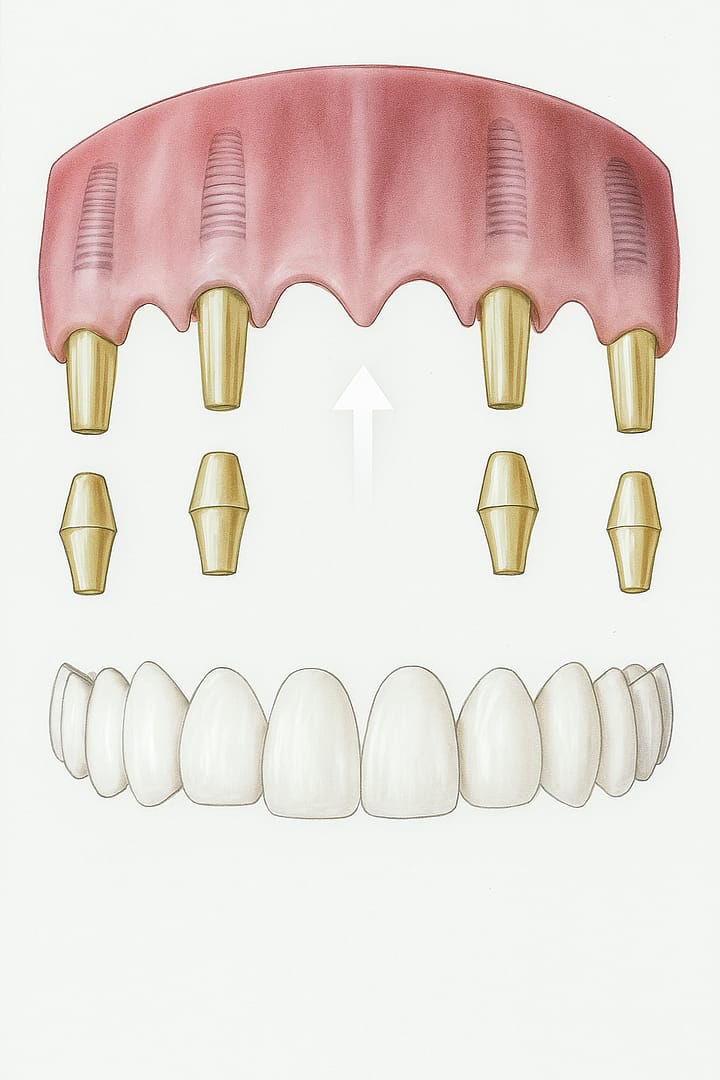

Prótesis total sobre implante

Reemplaza todos los dientes ausentes de una arcada completa. Se fija de forma atornillada sobre los implantes, brindando una solución fija, estética y funcional para pacientes con pérdida dental total.